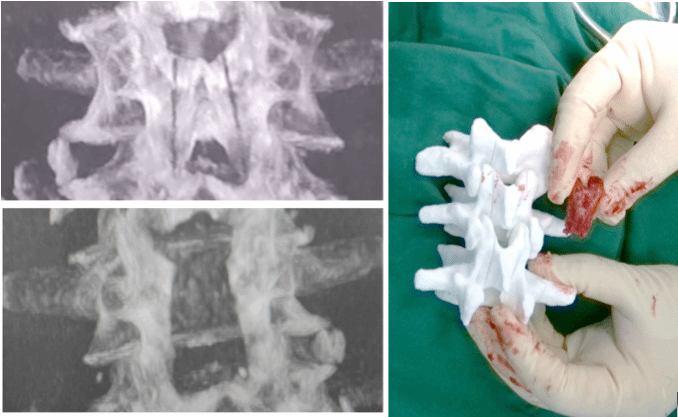

本次手术患者是一名老年男性,因为腰椎管狭窄症导致出现腰痛、双下肢疼痛麻木、间歇性跛行等症状。经过详细检查和评估,李危石教授团队决定为他进行腰椎后路机器人减压+融合内固定手术。

该系统是我国国家重点研发计划“智能机器人”主题项目“面向脊柱椎板切除手术的机器人系统”的重要成果。系统率先融合基于切削能量的人体组织识别技术、基于深度学习的图像分割技术、精密机器人和导航位置跟踪技术,实现手术路径个性化智能规划、切削过程生物组织特征自动识别、骨组织精准自主切削等功能。

基于超声动力工具的椎板自主识切手术机器人系统

将机器人技术引入椎板切除手术,量化医生的手术经验和操作,通过配置手术需要的技术/装备、规范操作流程,解决椎板切除操作中神经/脊髓损伤和手术机器人自主操作能力不足等难题。